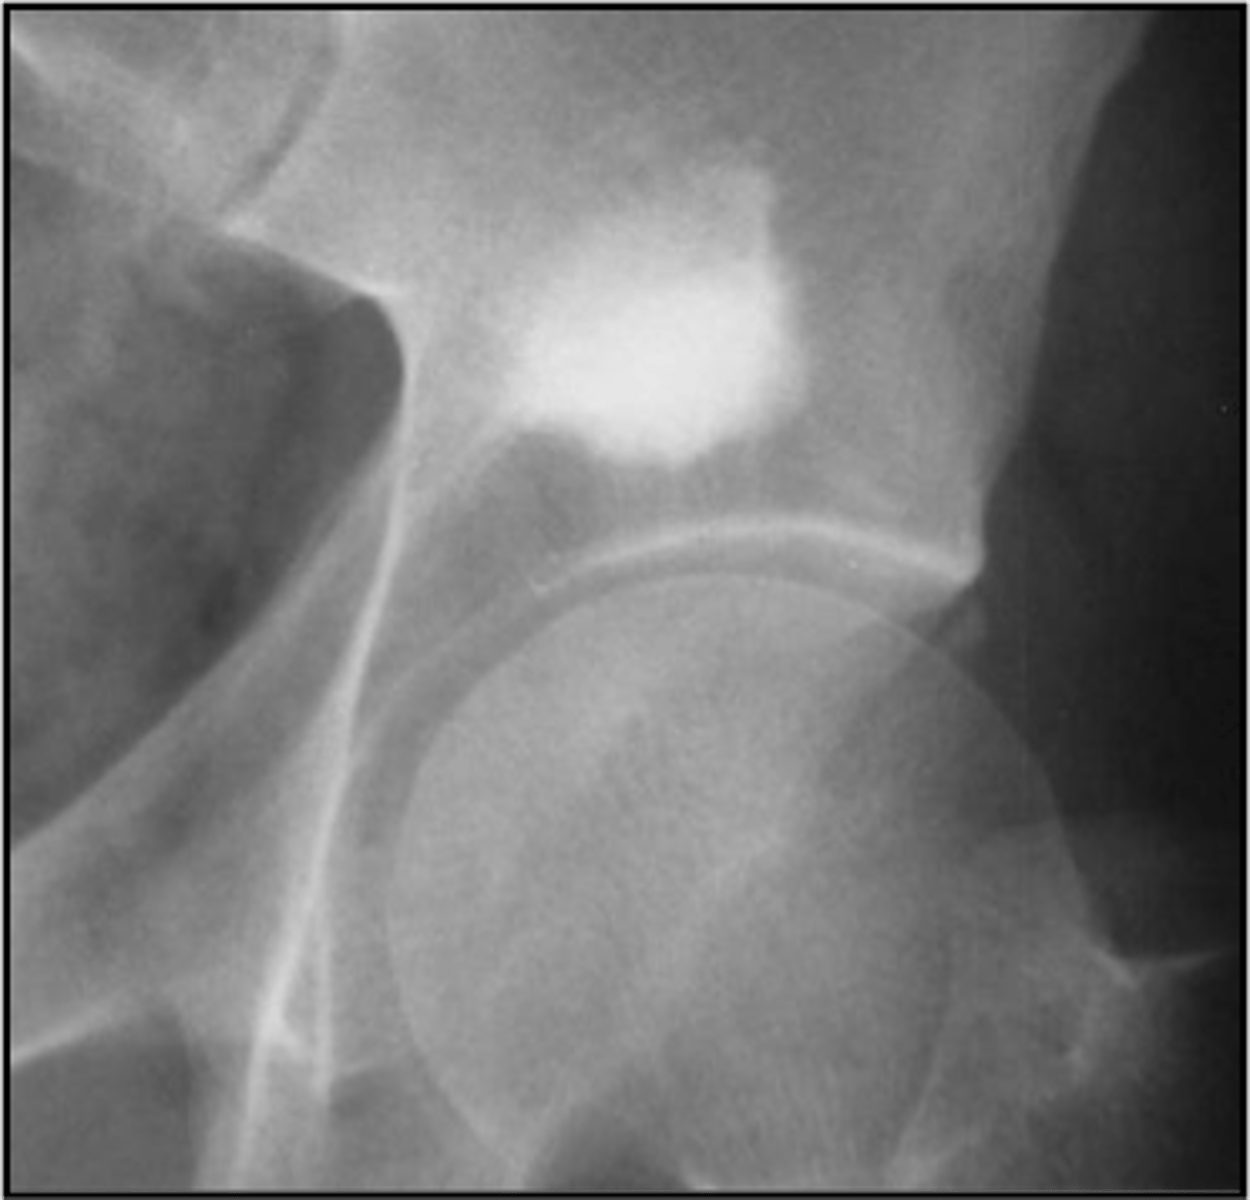

Osteoclastoma

Another term for giant cell tumor

- 80%

- 20%

Giant cell tumor pathology:

- _____ benign (F:M, 3:2)

- _____ malignant (M:F, 3:1)

<p>Giant cell tumor pathology:</p><p>- _____ benign (F:M, 3:2)</p><p>- _____ malignant (M:F, 3:1)</p>

- 20-40 y.o.

- Knee (tibia and femur)

- Localized pain and aching

- Joint pain and restricted motion

State the clinical features of giant cell tumor

- Osteolytic

- Geographic

- Multiloculated and septated

- Begin in metaphysis

- Extend to subarticular bone

- Expansion

- Eccentric

- Quasi-malignant (can't tell benign from malignant)

State the imaging features of giant cell tumor